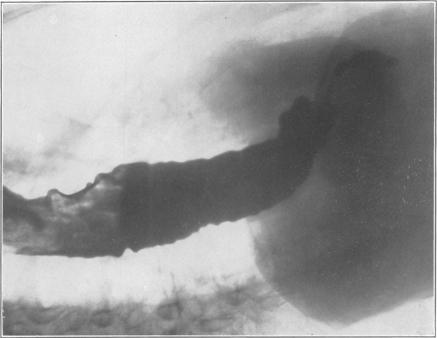

Cardiospasm.

Postgrad Med J. 1949 May;25(283):203-14. doi: 10.1136/pgmj.25.283.203.